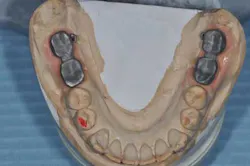

Figs. 6 a, b, c, and d: RPD framework try-in, bite record with mandibular implant-supported metal frameworks and mounting

- Try-in and final bite registration.